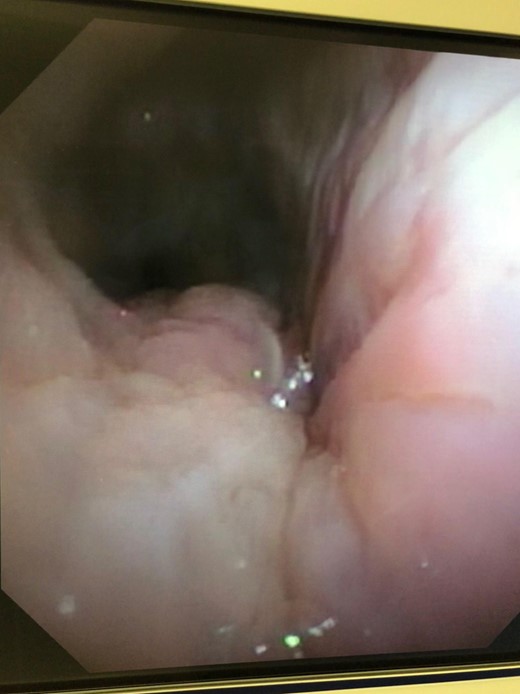

Ten days after the ACell® matrix placement, a rigid bronchoscope was again performed. Complete resolution of the defect had occurred. The Y-stent and the esophageal stent were removed the following week with resolution of symptoms. Repeat imaging following removal of the stents, including a non-contrast CT of the chest and a CT esophagram, demonstrated resolution of the fistulous communication. Repeat bronchoscopy was performed 10 months after stent removal with no evidence of fistula recurrence and minimal persistent inflammation (Fig. 6).